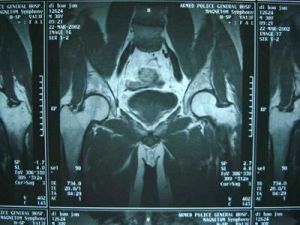

孩子跛行後,一般情況下如果損傷不嚴重,是可以自愈的。但有時跛行也可能潛伏著其他疾病,所以需要及時的治療,以免造成永久性的殘疾。起病緩慢,病程長。患兒數月來出現間歇性跛行與疼痛,疼痛常向膝部、大腿內側放射。症狀可因活動而加重,休息後緩解。部分病兒早期可無症狀或僅有輕微症狀,有時只有輕微步態異常,如行走時小腿內鏇。典型體徵為患髓有輕度屈曲內收畸形,伸直時,外展和內鏇受限。鏇轉髖關節時,有輕度肌肉痙攣。該病於活動期,症狀較明顯。約20%病例有外傷史,傷後急性發病,有破行,髖關節疼痛及活動受限,患肢短縮。通常伴有肌痙攣,以內收肌和髂腰肌最顯著。大腿及臀部肌肉有廢用性萎縮,髖關節活動受限,多為屈髖、外展外鏇動作,即“4”字試驗陽性。有時會出現固定的屈曲內收畸形。臨床上有三個重要體徵,即肥胖、髖關節活動範圍減小和內收肌痙攣。本病至晚期,症狀逐漸緩解,以至於消失。關節活動可恢復正常,或僅留外展和鏇轉活動受限和大粗隆膨突。臨床表現不一定與x線所見一致,有時在x線片上顯示股骨頭明顯畸形但症狀很輕,甚至無症狀,這可能表明髖臼對畸形的股骨頭已相適應。

早期診斷非常重要,對4一10歲兒童,凡不明原因的破、膝部疼痛與被行,病兒身材矮小,有反覆發作病史;早期x線片見到股骨頭內下緣至髖臼下緣的“淚滴”的距離增寬超過2mm,應按觀察髖處理,讓患兒3—6月內定期來門診由專科醫師隨訪檢查,直至除外Perthes病為止。拍攝高質量x線片是早期診斷該病不可缺少的條件,近年來有人使用同位素掃描對本病早期診斷,若有骨壞死,局部缺血區可出現所謂冷區,修復期血管增生,有新骨形成,就出現核素密集,出現所謂熱區,與健側比較,可測知股骨頭的供血狀態。這方面比一般x線片檢查所獲得的陽性徵要早2—5個月。其確診率高達95%。